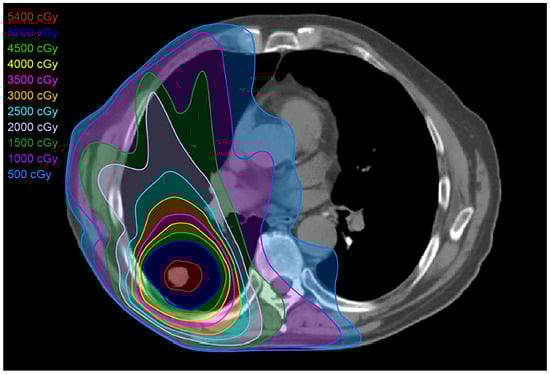

2.2. Three-Dimensional Conformal Radiotherapy

2.3. Intensity-Modulated Radiotherapy